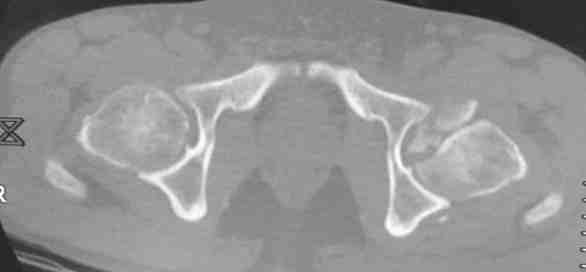

Мужчина, 50 лет, активный, падение с высоты. При поступлении вправление вывиха, других повреждений нет Без значимой сопутствующей патологии, не курит. Стоило ли выполнять остеосинтез при таком оскольчатом переломе или сразу пойти на ТНА?

На снимке №2 есть перелом заднего края суставной впадины,его, я так понял, решили не фиксировать? Фрагмент не очень большой.